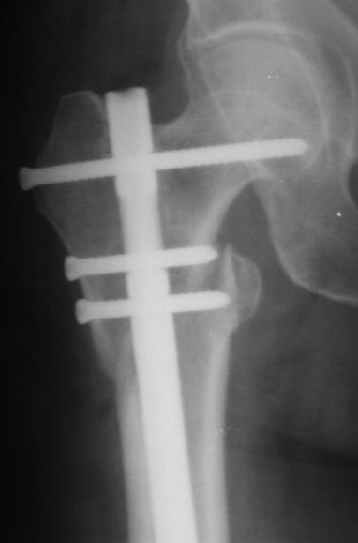

Женя, эта картинка показывает не оптимальное лечение вертельных переломов в моем представлении, а особенности дизайна упомяутого фиксатора.

В частности, его возможности при фиксации переломов проксимального отдела бедра - в сравнении с другими, имеюшими лишь по одному статическому и динамическому отверстию и с кондуктором для введения 2 винтов.

Это было года 2,5 назад, мы тогда еще уточняли возможности шинирования с угловой стабильностью гвоздем с поперечным расположением винтов при переломах проксимального отдела бедра. Пациенту не пришлось приобретать намного более дорогой рекон или проксимальный гвоздь. В приложении еще несколько примеров применения того гвоздя при высоких переломах бедра, в том числе с более латеральной точкой входа. Гвоздь изгибаем для этого.